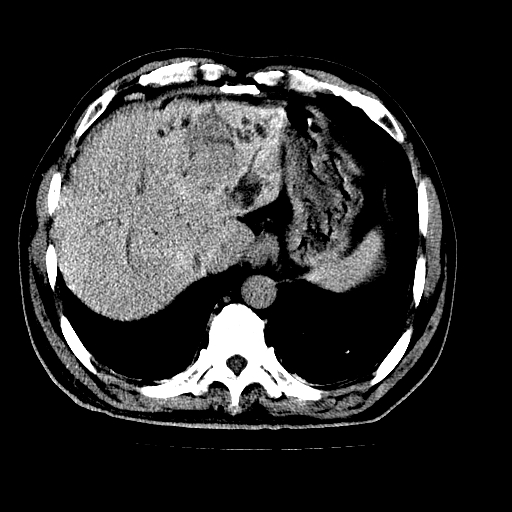

男,66岁,上腹部不适、黄染一周。彩超示:肝左叶占位,肝内胆管扩张,胆总管扩张,胆总管占位?

肝左叶不规则软组织肿块影,边缘不规整邻近肝实质受累分界不清;肝内胆管(左叶)明显扩张成“软藤状”,诊断:肝左叶胆管细胞癌。

肝左叶占位性病变,并胆管扩张,符合胆管细胞癌ct表现,门脉左支受累,左肾囊肿。窗宽太窄了,其他的看不清

左叶胆管细胞癌累及胆总管,门脉左支受侵,慢性胆囊炎胆结石,左肾小囊肿

肝左叶不规则软组织肿块影,边缘不规整邻近肝实质受累分界不清;肝内胆管(左叶)明显扩张成“软藤状”,诊断:肝左叶胆管细胞癌。胆囊钙乳症。